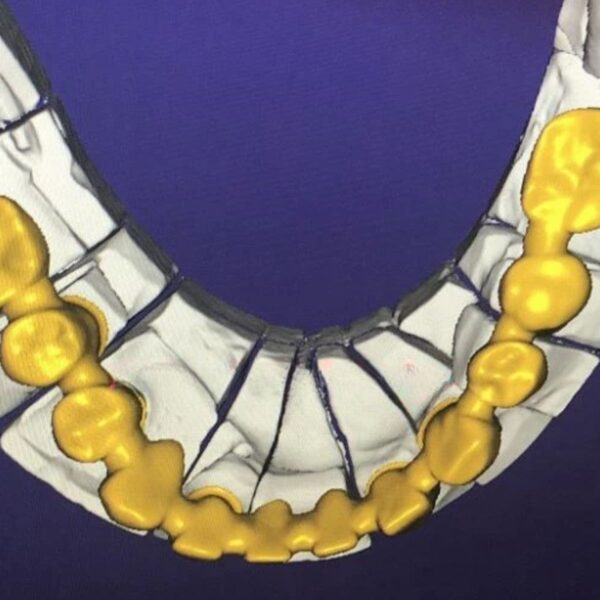

China Dental Design Complex Case Gallery

Challenging Projects That Showcase Our China Dental Design Expertise

Dental Crown Design

Advanced China Dental Design Capabilities

Our expert China Dental Design team delivers precision, quality, and cost-effectiveness for every complex restoration project